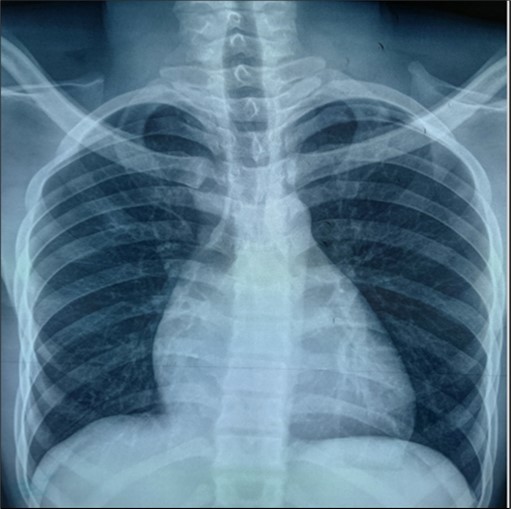

The frontal chest X-ray showed cardiomegaly with a cardiothoracic index of 0.7. The thoracic cavity and pulmonary parenchyma were without abnormality (Figure 1).

Figure 1.Frontal chest radiograph showing cardiomegaly

Cardiomegaly is frequent in Ebstein’s anomaly. A cardiothoracic ratio of at least 0.65 is associated with a poor prognosis 8 . This was the case with our patient.